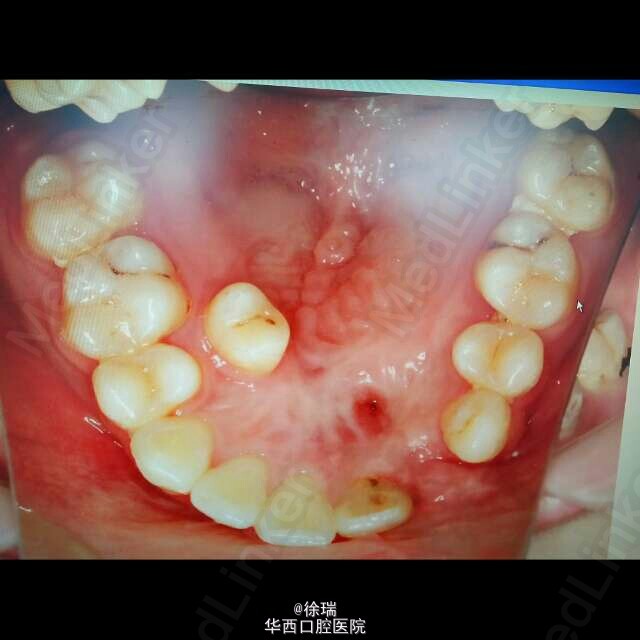

腭裂

每一个患有唇腭裂的小孩都是折翼的天使,从一出生就意味着漫长的序列治疗过程,唇裂修复术,早期正畸矫形,腭裂和/或牙槽突裂修复术,一般由于上颌牙槽骨术后瘢痕收缩,牙弓发育受限,牙量和骨量发生严重不调,这些孩子还要接受多年的甚至多期的正畸治疗,甚至再次外科修补术以恢复正常的外观和咬合。由于口腔多年处于戴托槽的情况,口腔卫生状况一般不佳。今天在临床第一次遇到了一个接受了多年正畸治疗的唇腭裂患者。